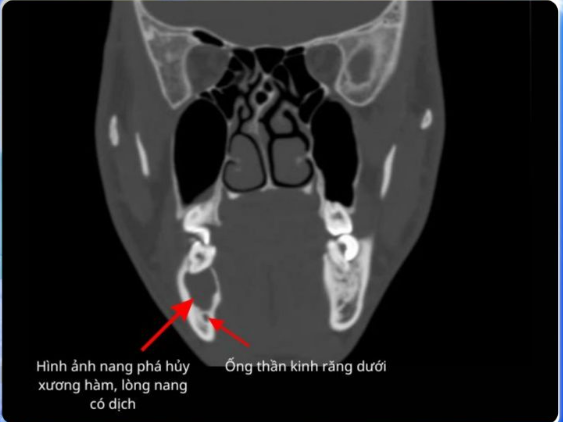

Tại khoa Răng Hàm Mặt, bác sĩ ghi nhận khối phồng má phải khoảng 5×2 cm, mềm, ấn lõm; răng 46 sâu nặng, răng 45 và 47 lung lay, chọc hút ra dịch vàng đậm. CT cho thấy nang lớn kèm phá hủy xương hàm dưới. Nếu chậm trễ, nguy cơ ảnh hưởng ống thần kinh răng dưới gây tê bì vùng má.

Hình ảnh răng sâu dẫn đến nang lớn kèm phá hủy xương hàm dưới - Ảnh BVCC